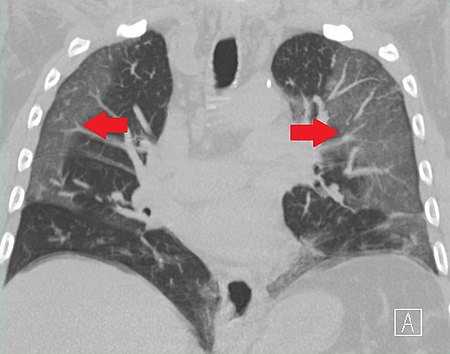

COVID-19 poate inițial să se prezinte asimptomatic sau cu puține simptome, iar ulterior poate dezvolta febră, tuse, dificultăți de respirație, dureri musculare și oboseală, urmate de pneumonie, sindrom de detresă respiratorie acută și deces. Nu există nici vaccinuri, nici tratamente eficiente, iar eforturile sunt de obicei limitate la ameliorarea simptomelor și măsuri de susținere.